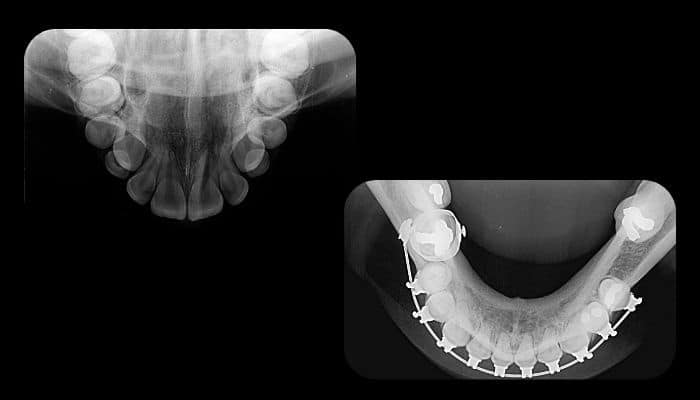

Imagem expandida para avaliação de dentes inclusos e estrutura óssea

A radiografia oclusal é um exame complementar que permite a visualização ampliada das arcadas dentárias e suas estruturas adjacentes. Indicada para a localização de dentes inclusos, identificação de fraturas e diagnóstico de anomalias dentárias, essa técnica fornece informações detalhadas para diversas especialidades odontológicas.

Esse exame é indicado principalmente para localizar dentes inclusos, avaliar fraturas coronárias e monitorar a erupção dentária, sendo muito utilizado em odontopediatria, ortodontia e cirurgia bucomaxilofacial.